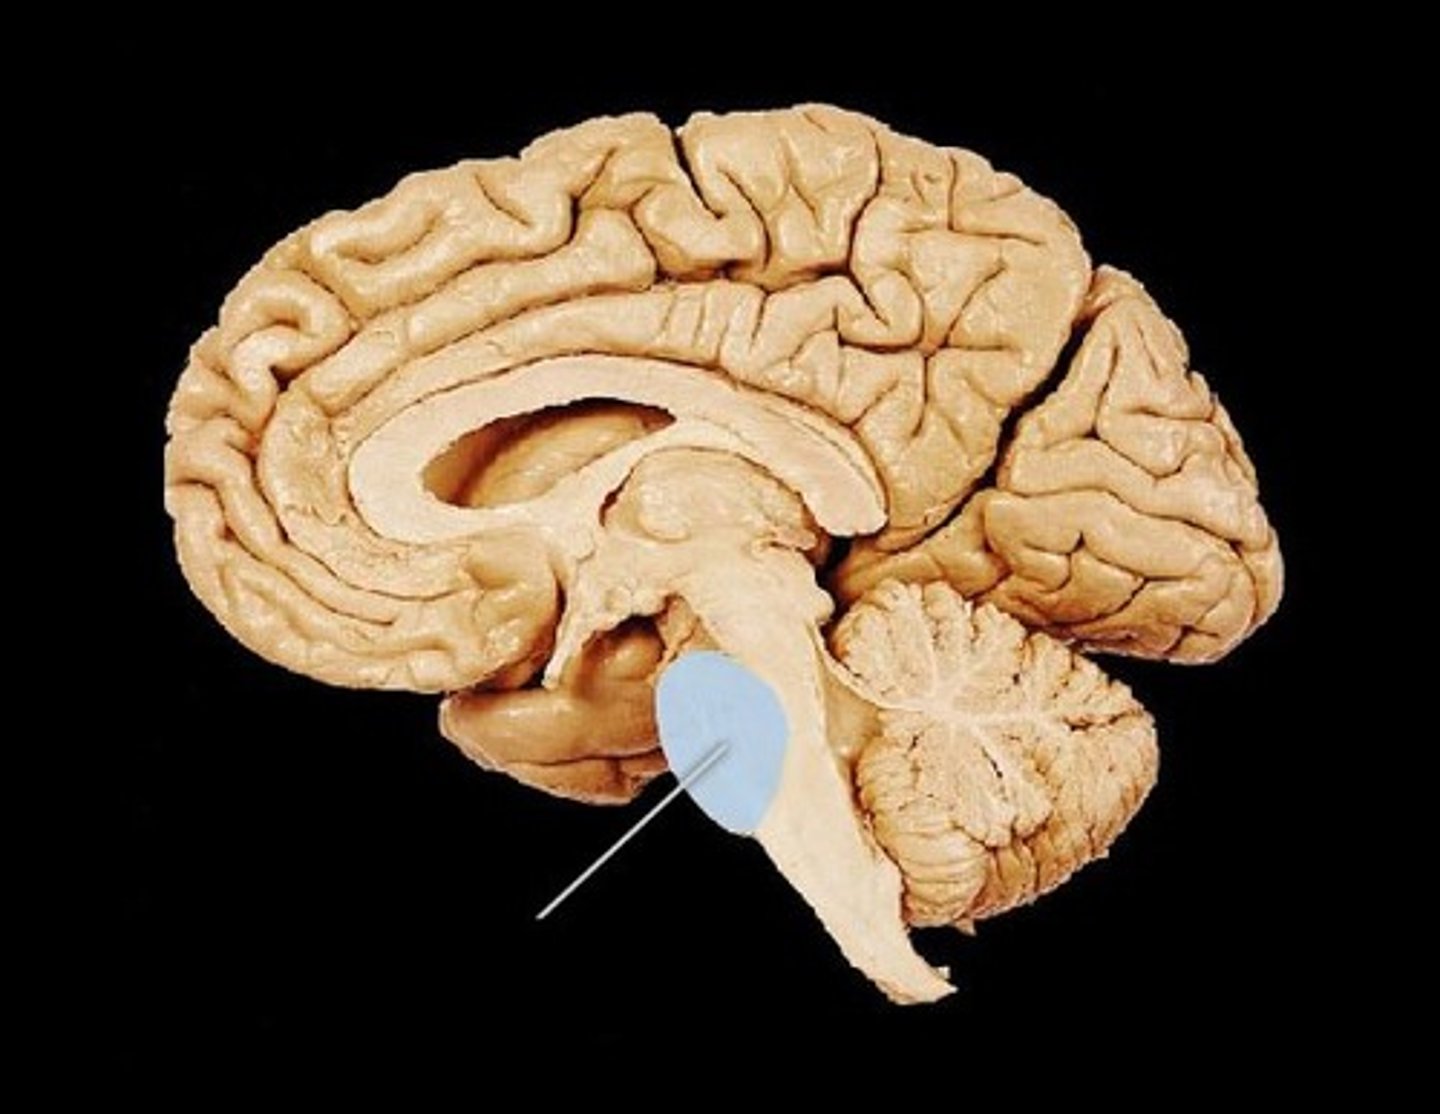

pons

contains sensory and motor tracts that connect brain to spinal cord

brainstem nuclei, respiratory muscles (rhythm)

medulla oblongata

brainstem nuclei, vital centers for control

of respiratory rate and cardiac function (heart rate/strength)

has sensory and motor tracts

gagging and vomiting center

cerebellum function

fine tuning of skilled voluntary motor activity to produce smooth, accurate movements

balance, equilibrium, and skilled movement

meninges function

protect brain and spinal cord

pia mater

deepest meninge, follows every contour of the brain

arachnoid mater

middle meninge, collagen and elastin fiber, spider web look

dura mater

made up of tough fibrous connective tissue, made up of the periosteal layer (creates periosteum of skull bone)

subarachnoid space

filled with cerebrospinal fluid